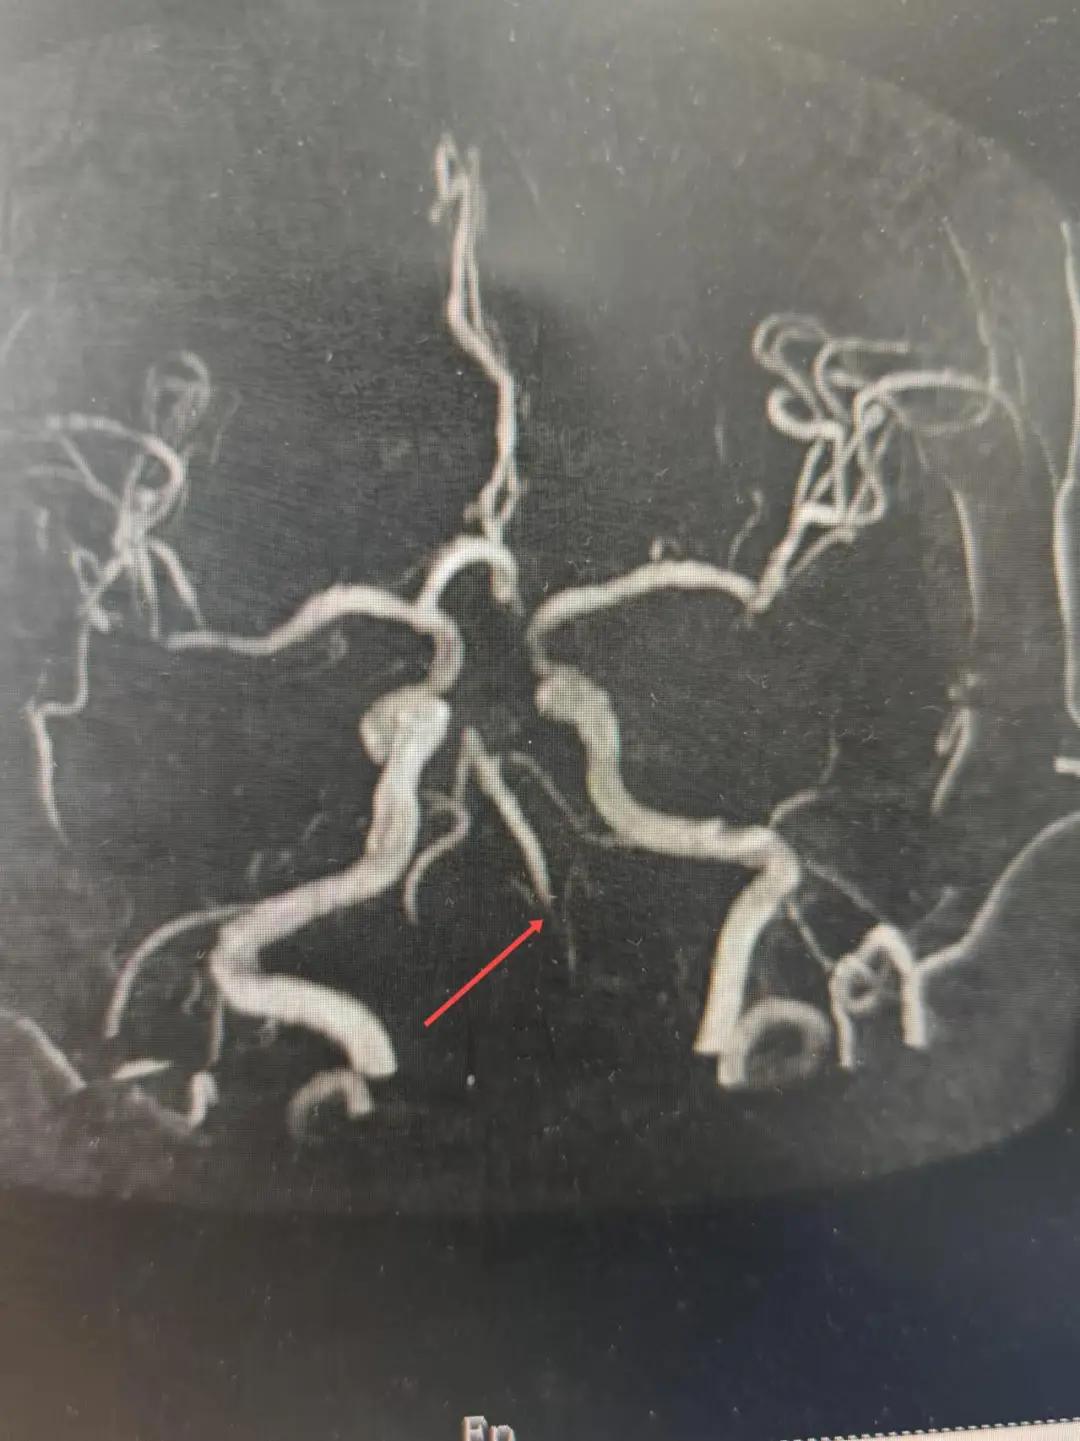

磁共振MRA提示基底動脈閉塞

2024年12月19日,漯河市中醫(yī)院腦一科收治了一位79歲的女性患者?;颊咴谌朐呵?小時出現(xiàn)言語不利,右側(cè)肢體無力。腦一科醫(yī)師關(guān)卓杰接診后,全面評估患者病情,給予其靜脈溶栓,并急查頭顱MR。影像可見腦干、雙側(cè)枕葉、左側(cè)海馬旁回及丘腦新發(fā)梗塞灶,基底動脈閉塞?;颊咴陟o脈溶栓完畢后仍出現(xiàn)陣發(fā)性言語不利、右側(cè)肢體無力、頭暈。立即進行科室間會診,副主任醫(yī)師彭壯考慮患者出現(xiàn)上述癥狀與其基底動脈閉塞后顱內(nèi)動脈代償不良有較大關(guān)系,且基底動脈閉塞有較高的致死率與致殘率,建議行急診取栓,降低患者死亡及殘障風(fēng)險。家屬了解病情,知情同意后要求行介入治療。